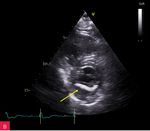

Rycina 2A, B. Zmiana u podstawy tylnego płatka mitralnego, obejmująca jego nasadę, a także fragment mięśnia ściany dolno-bocznej lewej komory w projekcji przymostkowej w osi długiej LAX (A) oraz w projekcji zmodyfikowanej, w której lepiej uwidoczniono hiperechogeniczną uwapnioną otoczkę zmiany oraz powodowany przez nią cień akustyczny (B)